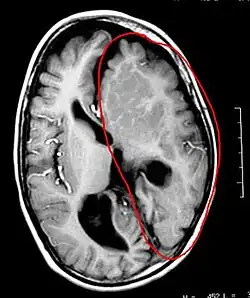

A hemisferectomia é um procedimento neurocirúrgico no qual um hemisfério cerebral (metade da parte superior do cérebro, ou cérebro) é removido ou desconectado. É usado para tratar uma variedade de distúrbios convulsivos refratários ou resistentes a medicamentos (epilepsia).[1]

É possível parar as crises removendo a área que as produz, caso isto possa ser feito com segurança, sem danificar funções vitais. A Lobectomia remove uma área pequena do cérebro. Entretanto, em poucos casos, um paciente pode ter doenças cerebrais graves somente de um lado do cérebro, que produz crises incontroláveis e paralisias no lado oposto do corpo. Neste caso uma operação mais extensa e delicada deve ser feita, a hemisferectomia, removendo todo ou quase todo o hemisfério cerebral.

Muitas vezes, o foco ou focos epilépticos não estão apenas em uma restrita área do cérebro, mas sim ocupando um hemisfério inteiro (como nos casos de malformação cerebral extrema chamada de hemimegalencefalia, ou nos casos de isquemia cerebral intra-uterina).